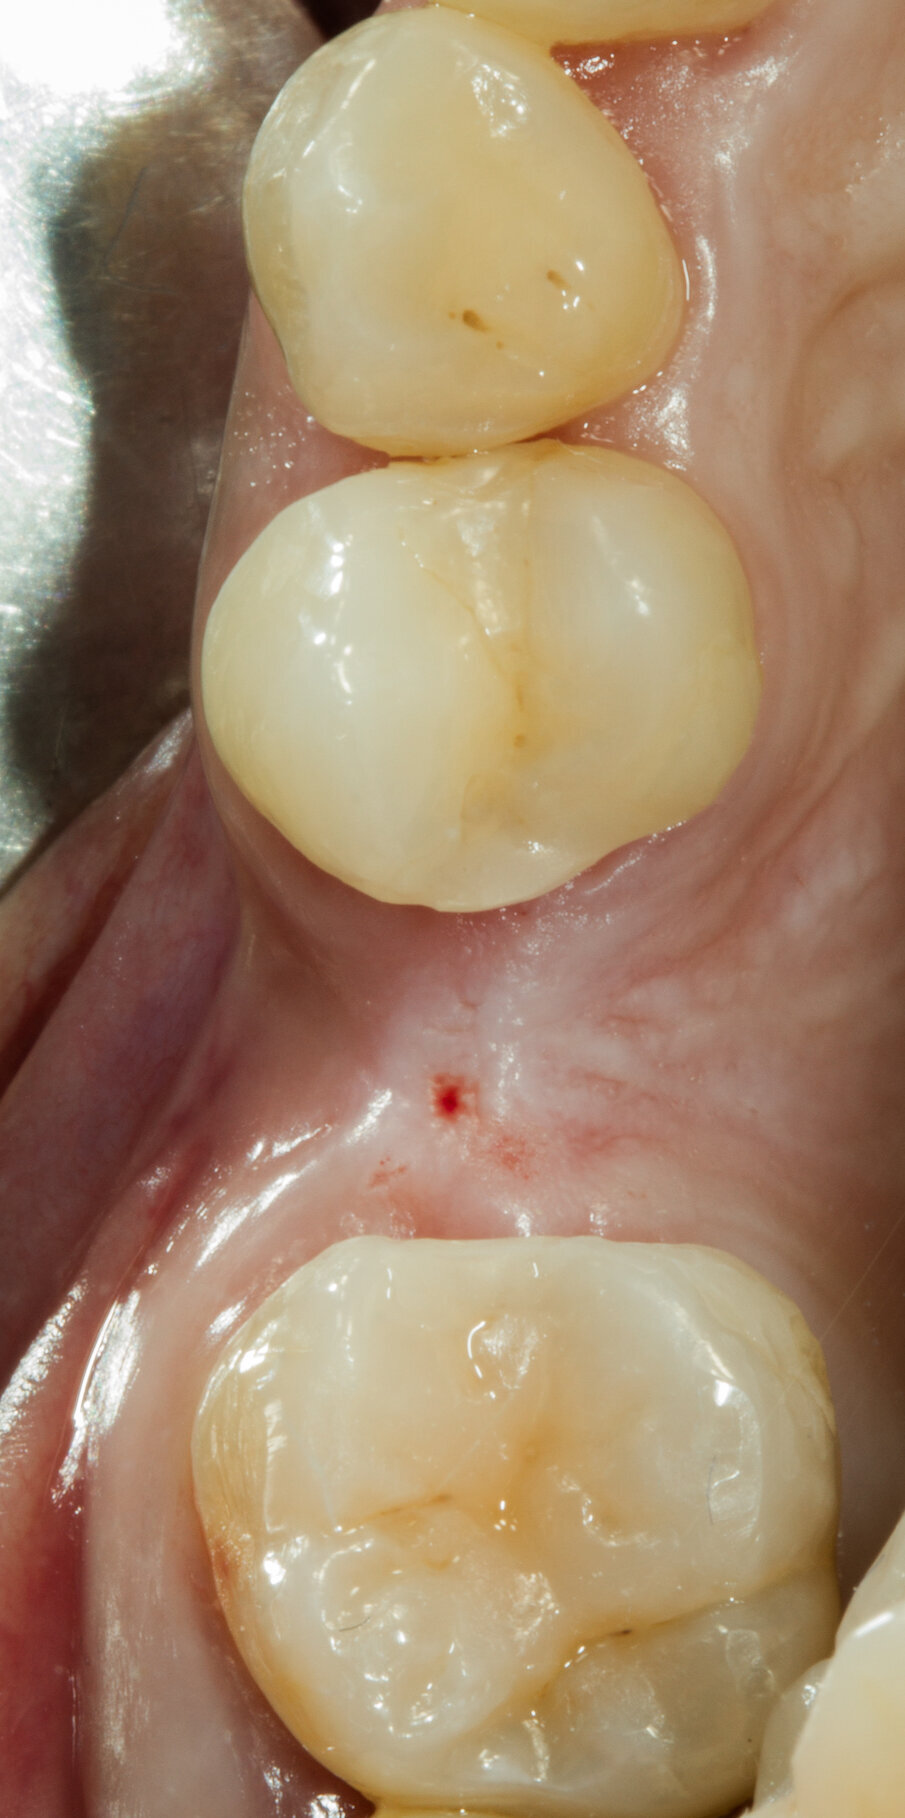

Dopo aver passivizzato il lembo si esegue una sutura a materassaio orizzontale e punto staccato centrale sulla parte crestale e suture semplici sulle incisioni di scarico (Figg. 13, 14). Dopo 10 mesi di guarigione si può procedere all’intervento di posizionamento implantare (Figg. 15-17). Sia dalle fotografie a lembo aperto (Figg. 18, 19) e da quelle di confronto tra la situazione alla baseline e dopo rigenerazione della cresta ossea (Figg. 20, 21) si può valutare come si sia ricostituito un osso ben corticalizzato, vascolarizzato, che ha riempito tutto il difetto osseo preesistente.

Fig. 16 - Situazione clinica a 10 mesi.

Fig. 17 - Vista vestibolare.